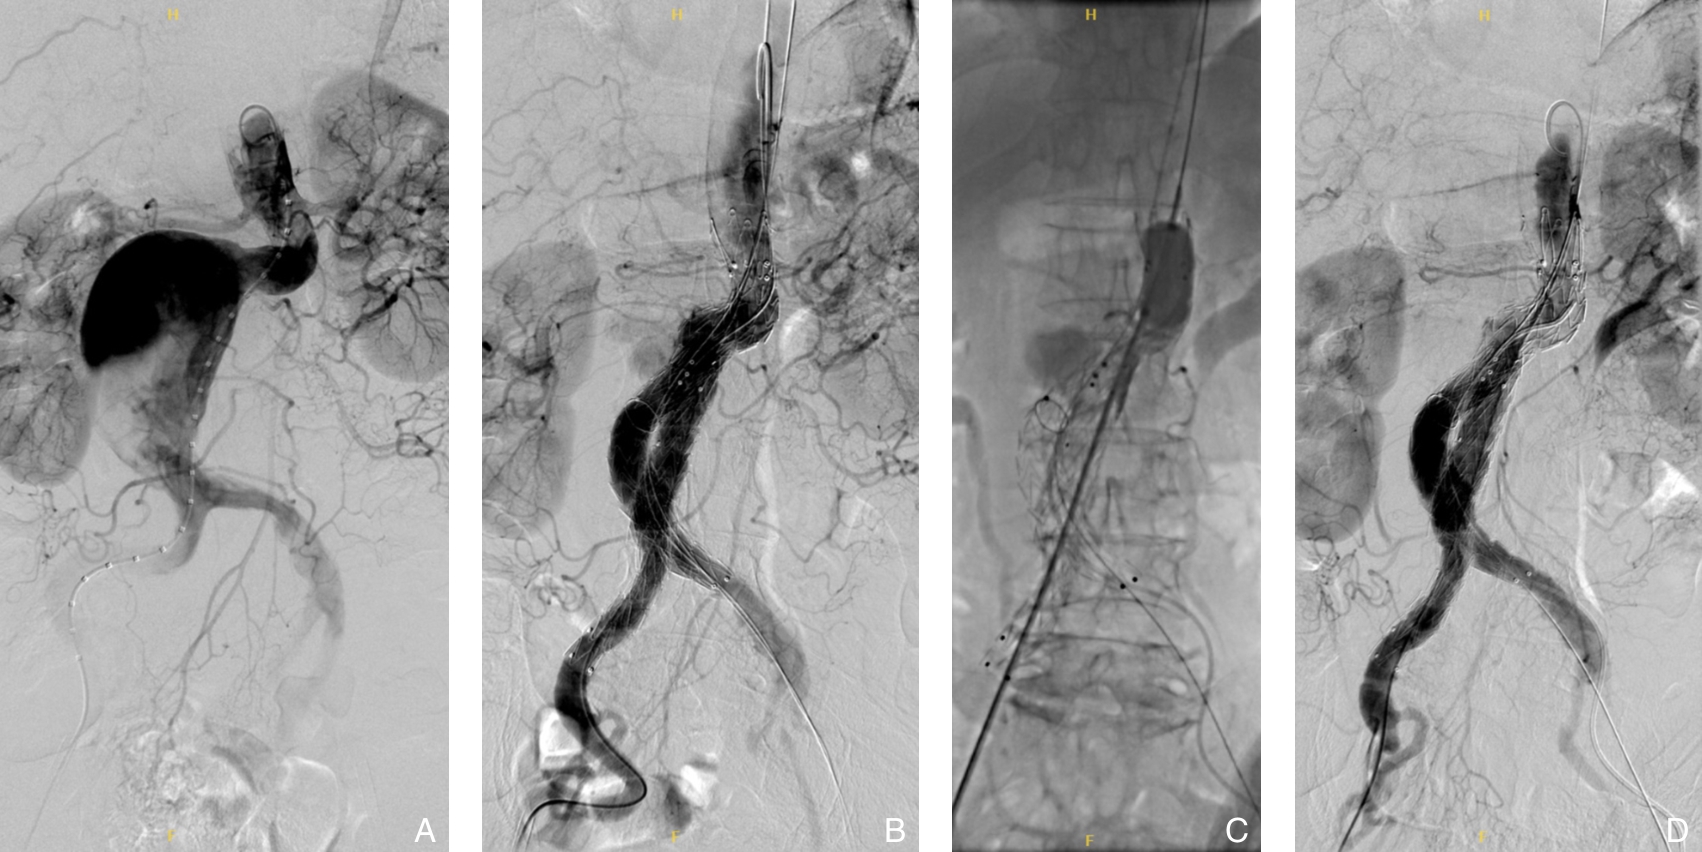

摘要:背景与目的 自发性孤立性肠系膜上动脉夹层(SISMAD)是一种较为常见的内脏动脉夹层疾病,主要表现为急性腹痛,严重者可引发肠缺血甚至坏死。随着CT血管成像(CTA)等影像技术的普及,SISMAD的检出率显著提高,但目前针对其治疗策略仍存在争议,尤其在保守治疗与腔内介入治疗之间的选择缺乏统一标准。为探讨两种治疗方式的临床效果及适应人群,本研究回顾性分析本中心SISMAD患者的临床资料,并比较不同治疗方式的短中期疗效,为制定个体化治疗策略提供依据。方法 回顾性分析2018年1月—2023年12月浙江省宁波市第二医院确诊的174例SISMAD患者临床资料,其中保守治疗30例,腔内介入治疗144例(包括支架植入和部分假腔弹簧圈栓塞联合支架植入)。术前均行CTA或肠系膜上动脉造影并分型。随访评估患者术后1个月和1年症状缓解情况及影像学指标,包括夹层重塑率、支架通畅性等。结果 保守治疗组1个月症状缓解率为90.0%,1年为92.8%;介入治疗组分别为99.3%和98.6%。1个月症状缓解率差异具有统计学意义(P=0.016),1年症状缓解率差异无统计学意义(P>0.05)。分型亚组比较中,介入治疗组各型症状缓解率普遍高于保守治疗,但差异均无统计学意义(均P>0.05);保守治疗组Ⅲ型患者症状控制较差,出现死亡病例。介入治疗成功率为99.3%,1年内支架移位或闭塞为0例,完全重塑率为86.8%,支架通畅率为100%。部分患者支架内出现少量附壁血栓,未见血流阻断。结论 腔内介入治疗对SISMAD患者具有较高的技术成功率和良好的短中期疗效,尤其适用于真腔血流受限的Ⅱ型及Ⅲ型患者。建议根据夹层分型及血流受限程度,个体化制定治疗方案,以提升疗效、降低风险。